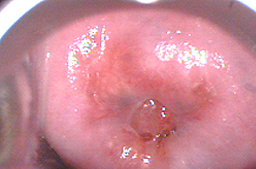

NIC 2 o Displasia moderada asociada a infección por VPH

Neoplasia Intraepitelial de Cérvix grado 2 o Displasia moderada.

• Fotovaporización con láser CO2

• Cicatriazación al mes del tratamiento

• Cicatrización al sexto mes del tratamiento